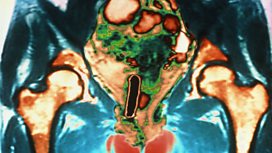

Ovarian Cancer

Women who survive ovarian cancer are seldom given any help with their sex life.